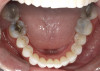

A 52-year-old female patient with history of lost retainers that she had used for a previous orthodontic treatment presented with minor orthodontic relapse during a hygiene visit. Her chief concern was that her lateral incisors were "starting to flare forward," as she had not been compliant with her retainers, and she expressed a desire for an affordable clear aligner solution. Clinically she presented with upper and lower anterior tooth crowding of less than 3 mm, specifically lower anterior teeth Nos. 23, 24, and 25, with a reverse curve of Spee of less than 2 mm on the lower anterior teeth (Figure 1 through Figure 3). The upper anterior arch presented with lateral incisor buccal rotations of less than 15 degrees on teeth Nos. 7 and 10 from an overjet view (Figure 4). The patient's oral hygiene was within normal limits, with stage one gingivitis, based on the new multidimensional staging and grading system of the American Academy of Periodontology and the European Federation of Periodontology that was adopted in 2017.12 The patient also presented with class I bite classification with gingival abfraction on both the anterior and posterior arches, with visibly missing class V restorations (Figure 5 and Figure 6).

Fig 3. Patient presented with upper and lower anterior tooth crowding

of less than 3 mm. Figure 1: Anterior view. Figure 2: Upper arch. Figure 3: Lower

arch.

Figure 3